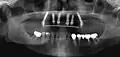

Implants en place. Notez qu'il y a moins d'implants que de dents sur la prothèse.

Prothèse totales fixes sur implants

Elles ont en règle réalisables sur six implants (selon des modalités bien précises pour l'observation desquelles le poseur d'implant doit avoir les qualifications requises). Selon la récession osseuse du patient à la suite de la perte de ses dents, on réalisera une prothèse sans ou avec fausse gencive. Moins coûteuses que les bridges, ces prothèses sont moins longues à réaliser. Rien n'empêche cependant le patient de faire remplacer sa prothèse résine par une prothèse céramique après une période d'observation de deux ans.

Radiographie des six implants